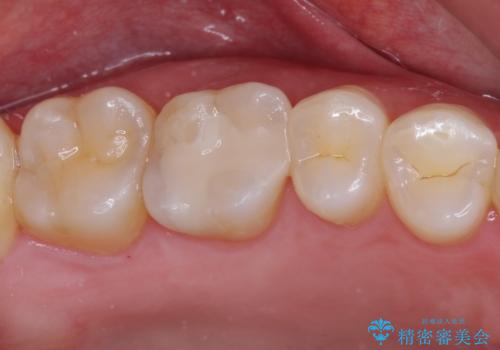

- 銀歯をセラミックにしたいとのことで来院された患者様です。

まず麻酔をして銀歯を外し、むし歯を除去し、形を整えて型取りします。

そして次の来院時、セラミックインレーを装着し、噛み合わせなどの調整を行います。

それを左右に分けて行いました。

インレーを装着するときは、唾液や血液による接着力の低下を避けるためにラバーダム防湿を行いました。

自然な色調で大変満足されました。